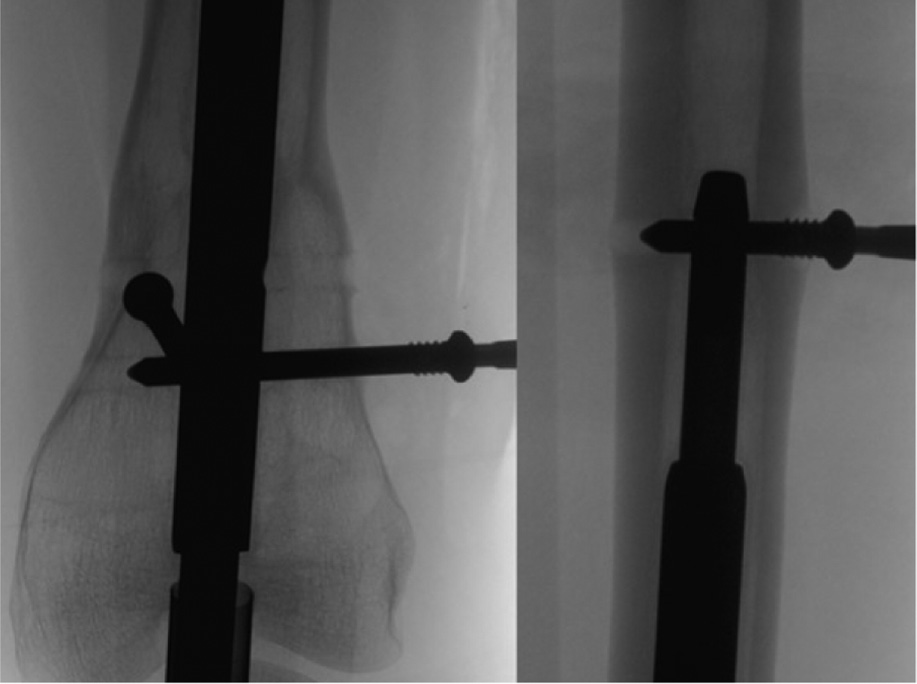

Figure 4. Rotate the limb until the distal interlocking elements are in perfect profile. This will help determine if there has been any bone growth over the top of the fixation elements that might preclude a percutaneous removal attempt. It is additionally advised to use this position to remove the screw. Placing the screwdriver in-line with the screw in perfect profile and perpendicular to the fluoroscopy beam will ensure proper orientation and facilitate engagement into the screw head.

jposna20220031_fig4.jpg